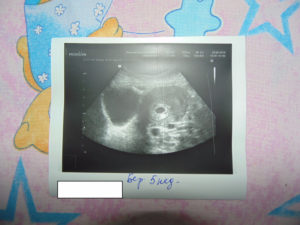

Если беременность 6 недель, коричневые выделения появились, постоянно мучают боли внизу живота, ухудшается общее состояние, необходимо сразу обратиться к врачу. При таких симптомах часто назначается УЗИ. При наличии беременности в матке причины такого состояния дополнительно выясняются. Если диагностирована внематочная беременность, ее необходимо устранить.

Причины этих явлений бывают опасными для здоровья мамы и плода. Но в любом случае нельзя впадать в панику, а нужно обратиться к врачу, пройти УЗИ и держать ситуацию под контролем. Четыре из пяти женщин, наблюдавших коричневые выделения на ранних сроках беременности, донашивают ее и рожают детей.

Редкая, но опасная ситуация – пузырный занос. При нем на УЗИ вместо плаценты в матке обнаруживают большое количество заполненных жидкостью пузырьков – кист. Выделения при беременности бывают коричневыми, желто-коричневыми, бурыми, с вкраплениями пузырьков. Женщины отмечают:

На шестой неделе ребенок похож букву С, у него начинают формироваться конечности, кровеносная система и мелкие сосуды, зарождается сердце, дыхательная система и другие органы. В полных шесть недель длина эмбриона превышает один сантиметр. На этом сроке появляется плодный пузырь.

Поэтому откладывать визит к гинекологу нельзя. При появлении любых необычных симптомов следует идти к специалисту. Он проведет комплексное обследование, сделает УЗИ и возьмет анализы. Помните, что на раннем сроке болезнь легче поддается терапии.

Если боль ощущается все чаще, появились коричневые выделения, стоит сходить к гинекологу и сделать УЗИ. Если угроза прерывания подтвердилась, потребуется лечение в стационаре. Безотлагательная медицинская помощь необходима при наличии следующих симптомов:

К сожалению, для некоторых женщин эти коричневые выделения свидетельствуют о выкидыше. Врач оценивает состояние пациентки с помощью ультразвукового обследования. Дополнительно женщина сдает анализ крови на содержание особого гормона — хорионического гонадотропина (ХГЧ). Все эти показатели становятся основанием для амбулаторного лечения будущей мамы или ее госпитализации.

Осторожно! Нет особых симптомов, чтобы отличить внематочную беременность от воспаления придатков, поэтому поможет определить диагноз только УЗИ.